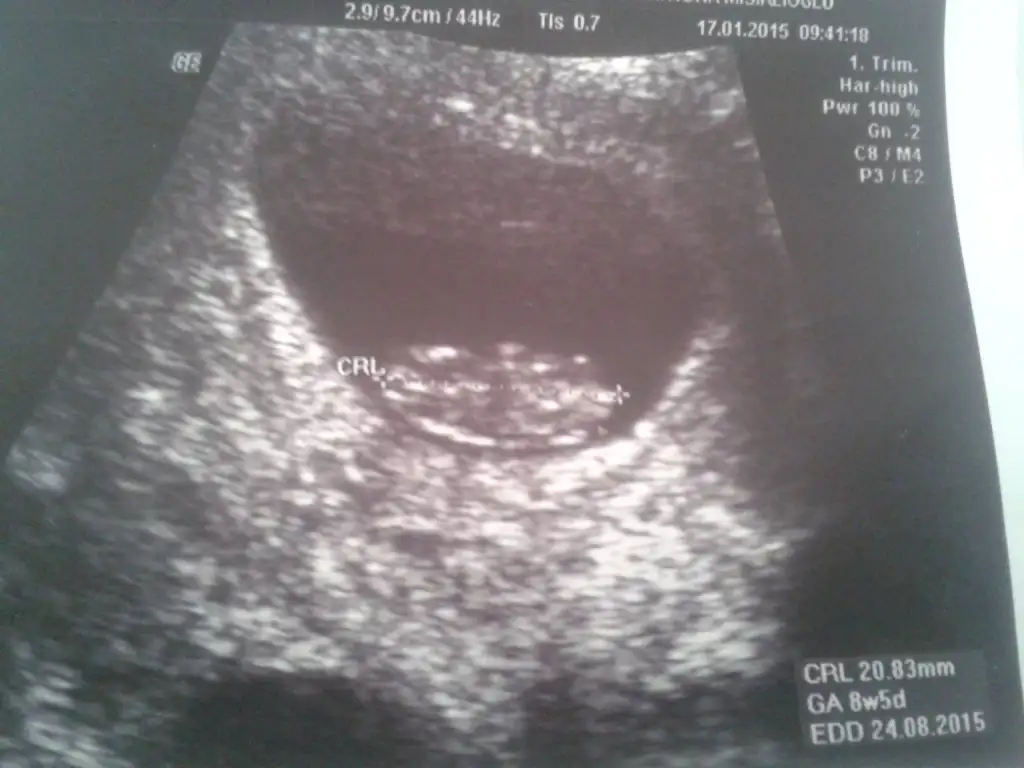

bu resim 8. haftanın sonu 9.haftanın ilk günüsoldaysa erkek, sağdaysa kız buradaki teoriye göre ama 7-8-9 haftalık ultrason görüntüsü olması gerekiyormuş. benim 7.hafta soldaydı 10.hafta sağa geçti. seninki kaç haftalık

bence sağda görünüyor ama parlak yer dediğini anlamadım başka fotoğrafı yok mu çok bulanık çıkmış doktorun boyunu ölçtüğü 2 nokta arası olanlarda daha rahat anlaşılıyor.Kizlar bu ultrasona gore ne sizce tahminlerinizi bekloyorum 8 haftalik burda altta gorunen parlak yer melegim

cnm benim bebegim içinde yorum yaparmısın 13+1bence sağda görünüyor ama parlak yer dediğini anlamadım başka fotoğrafı yok mu çok bulanık çıkmış doktorun boyunu ölçtüğü 2 nokta arası olanlarda daha rahat anlaşılıyor.

Canım baktım bebeğin sağda ama burada kesenin konumuna göre tahmininde daha erken (7-8-9. haftalar için)görüntüsü olması lazım. Benim bebeğim 7. haftada soldaydı 10.haftada sağa geçti. o yüzden yanıltabilir.cnm benim bebegim içinde yorum yaparmısın 13+1

çok teşekkürler cnm bu 8+5 günlüktüCanım baktım bebeğin sağda ama burada kesenin konumuna göre tahmininde daha erken (7-8-9. haftalar için)görüntüsü olması lazım. Benim bebeğim 7. haftada soldaydı 10.haftada sağa geçti. o yüzden yanıltabilir.

bu 12+0 canımCanım baktım bebeğin sağda ama burada kesenin konumuna göre tahmininde daha erken (7-8-9. haftalar için)görüntüsü olması lazım. Benim bebeğim 7. haftada soldaydı 10.haftada sağa geçti. o yüzden yanıltabilir.

Burada sağda gibi inşallah gönlünden geçtiği gibi olur. Bizim 13+2lik görüntümüz böyle doktor erkek dedi ama kesin değil. seninkiyle karşılaştır bakalım bende hiç anlamıyorumçok teşekkürler cnm bu 8+5 günlüktü